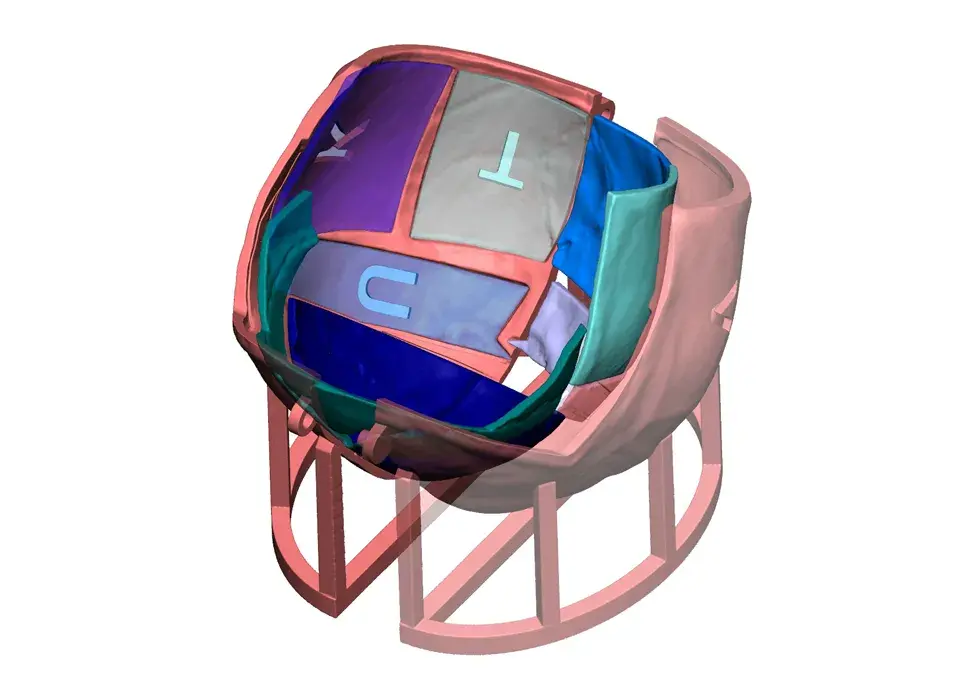

3D Systems' VSP® surgical planning solutions for craniomaxillofacial (CMF) applications received FDA clearance as a service-based approach to personalized surgery over 10 years ago.

3D Systems and Stryker Corporation have partnered to provide surgeons with best-in-class products and services for craniomaxillofacial surgeries. As a leader in personalized healthcare solutions, 3D Systems has planned and delivered devices for more than 140,000 patient-specific cases. The Stryker Craniomaxillofacial business specializes in providing patient-specific options and innovative solutions that help drive efficiencies in surgical suites. The combination of Stryker’s specialized team and advanced implants with 3D Systems' cutting-edge 3D printing technologies and expert consulting services positions both companies to provide a superior level of service to healthcare professionals who use these revolutionary solutions.